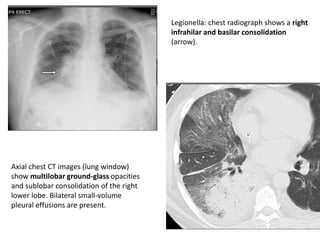

Axial chest CT images (lung window)

show multilobar ground-glass opacities

and sublobar consolidation of the right

lower lobe. Bilateral small-volume

pleural effusions are present.

Legionella: chest radiograph shows a right

infrahilar and basilar consolidation

(arrow).

Axial chest CTimages (lung window) show multilobar ground-glass opacities and sublobar consolidation of the right lower lobe. Bilateral small-volume pleural effusions are present. Legionella: chest radiograph shows a right infrahilar and basilar consolidation (arrow).